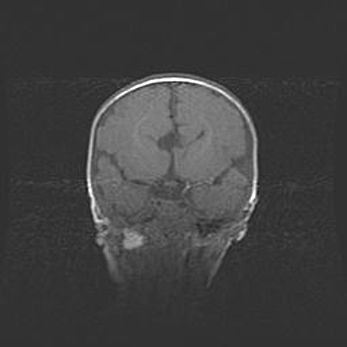

Церебральная ишемия II.

Возраст: 5 дней

Вес: 3400 г

Пол: женский

Окружность головы: 35 см

Срок гестации: 39 недель

Церебральная ишемия – это заболевание, характеризующееся недостаточностью (гипоксией) либо полным прекращением (аноксией) снабжения мозга кислородом по причине закупорки одного или нескольких сосудов. Это приводит к  что метаболическим расстройствам различной степени тяжести в тканях головного мозга, развитию коагуляционных некрозов и гибели нейронов.